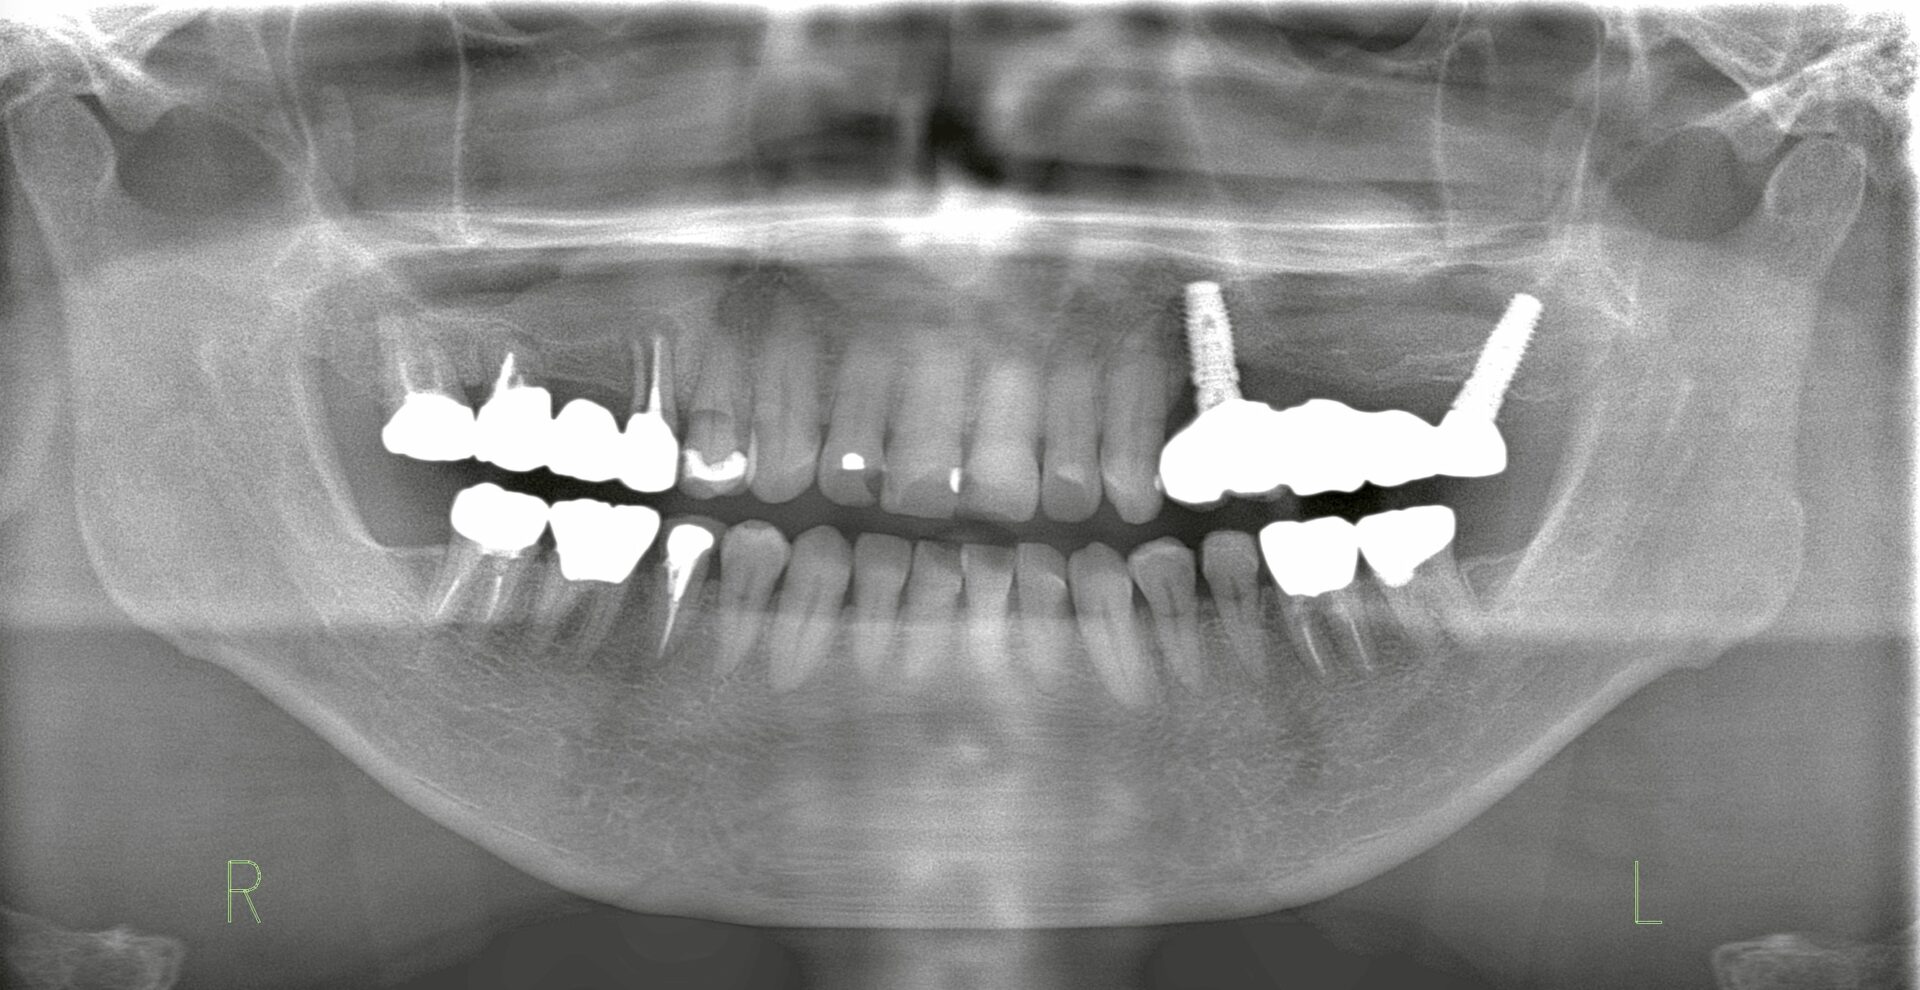

| 術前レントゲン写真 | ![]() |

| Consideration | 右上ブリッジは、歯根破折を認めるため抜歯を行った。その後骨の回復を待ってからインプラント治療を計画したが、上顎洞までの距離が短くサイナスリフトの必要性があった。既存骨は4mm認めるためサイナスリフトと並行し同時埋入を行った。5ヶ月の待機期間を経てブリッジ補綴へ。サイナスリフトはクレスタルアプローチテクニックで実施した。 |